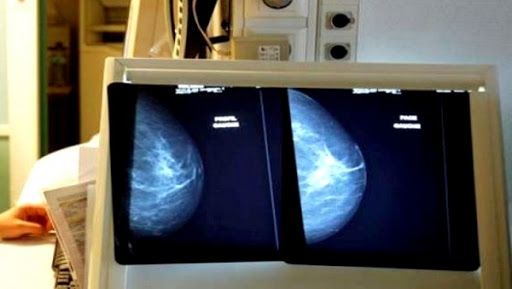

TIPASA- Une convention nationale pour la prise en charge des femmes atteintes du cancer du sein a été signée, lundi à Tipasa, entre l’Union nationale des femmes algériennes (UNFA) et l’Association algérienne pour la planification familiale(AAPF), a-t-on constaté.

L’accord, axé sur trois points, la sensibilisation, l’orientation et la prise en charge, engage l’Association co-signatrice, à « mobiliser son staff médical qualifié et ses structures pour la prise en charge de la santé des femmes, notamment celles atteintes du cancer du sein », a indiqué Mme.Hafsi.

Elle a ajouté que cette convention ciblera, dans une première étape la wilaya de Tipasa, avant sa généralisation à l’ensemble du pays. Elle a fait savoir que les bureaux de wilaya de l’UNFA procéderont au recensement des femmes atteintes du cancer du sein à leur niveau, avant de prendre contact avec l’Association algérienne pour la planification familiale, qui oeuvrera, de son côté, à leur faciliter les examens médicaux nécessités et à leur obtenir des rendez- vous pour leur prise en charge.

Les femmes rurales et les femmes, des régions reculées, au niveau d’instruction limité, sont, également, ciblées par cette convention, stipulant la sensibilisation, de cette catégorie sociale, à la nécessité du dépistage précoce de cette maladie.